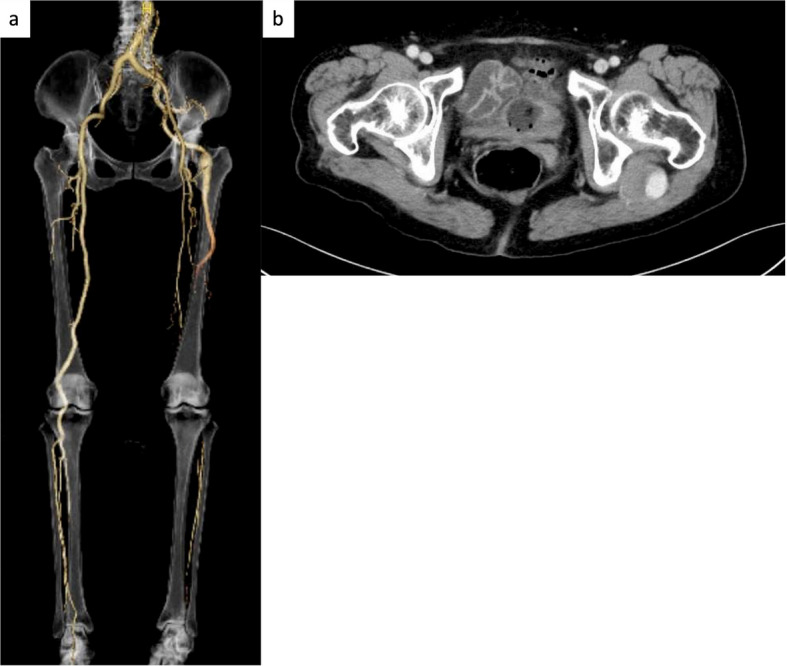

Case presentation: This case report details the treatment of two women (aged 89 and 82 years) with ALI associated with PSA. In both cases, reperfusion was achieved without CDT and stent grafts were deployed across the PSA aneurysm. The final angiogram showed that the PSA aneurysms had disappeared, and the vessel runoff was maintained. Both patients were successfully discharged from the hospital and experienced no complications over the next 6 months.